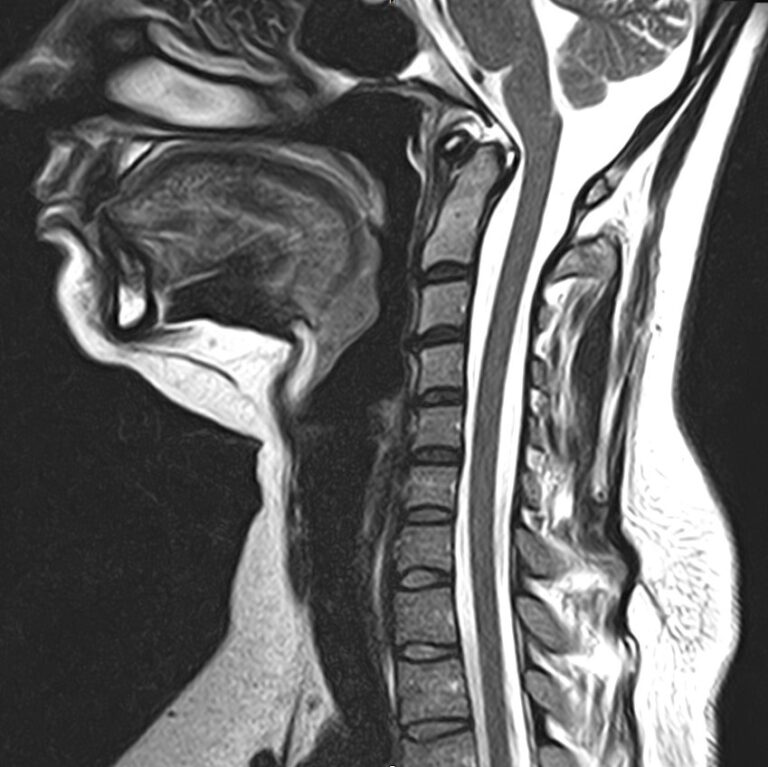

Для того, чтобы оценить состояние шейных позвонков с прилегающими тканями и одновременно визуализировать плечевой сустав, в нашей клинике выполняется комплексное обследование, включающее два протокола: МРТ шейного отдела позвоночника и МРТ плечевого сустава.

Метод МРТ позволяет оценить состояние всех анатомических областей шейного отдела позвоночника: костную структуру позвонков, спинной мозг с отходящими от него нервными корешками и окружающие мягкие ткани. Протокол обследования плечевого сустава включает оценку костной структуры, суставной капсулы, полости сустава с выстилающей его синовиальной оболочкой, связок, сухожилий, мышц и окружающих мягких тканей.